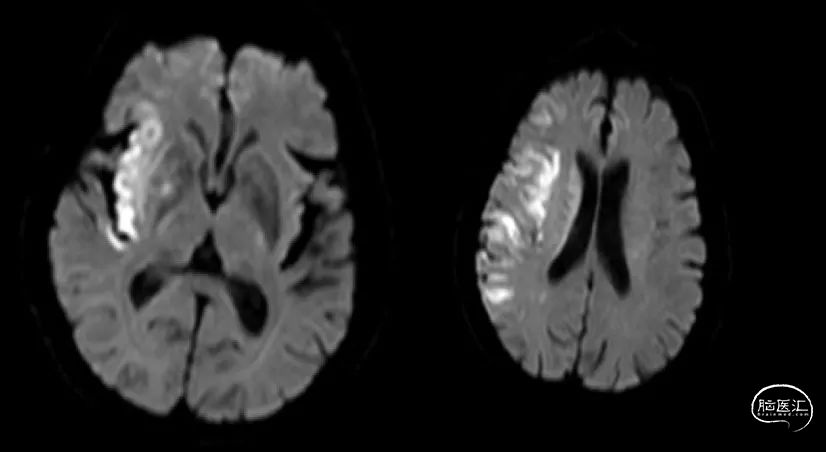

术后影像( 2021.7.8)

予以抗聚调脂降压和改善侧枝循环等治疗,术后9天出院。

症状:明显改善,肢体无力较前好转,言语清晰,无头痛、头晕,无胸闷、气促,无恶心、呕吐,无胸腹部等不适。精神、食纳可,大小便正常。

体查:四测正常,神志清,言语流利,双侧瞳孔等大等圆3mm,对光反射灵敏,颈软,脊柱四肢无畸形,左上肢肌力4-级,握力差,左下肢肌力4+级。右侧肢体肌力5级,肌张力正常。左侧病理均阳性。

NIHSS:3(面瘫1、上肢1、下肢1),洼田饮水实验1级,mRs3分。